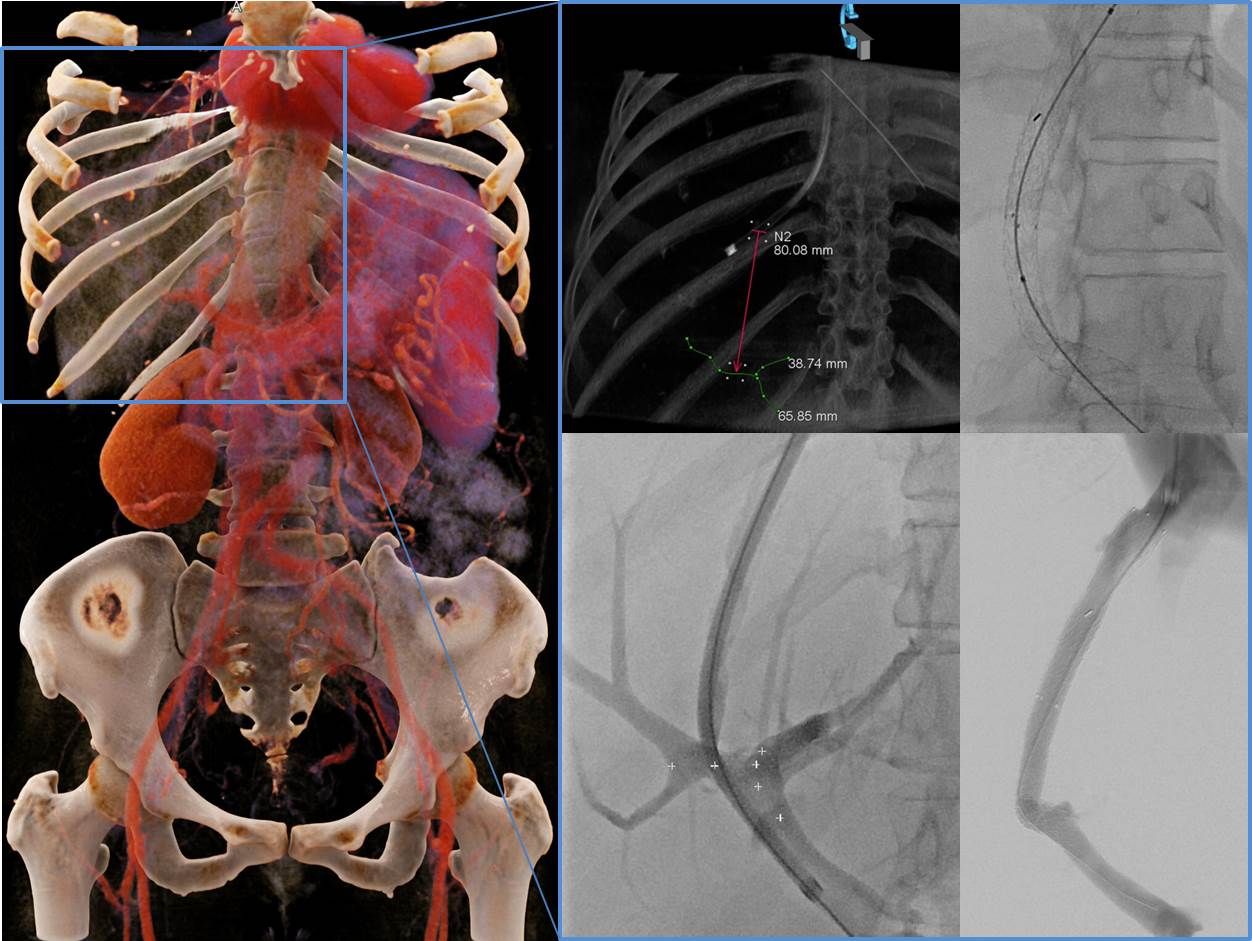

Darstellung der Gallenwege (Pfeile) über die einliegende Drainage (Pfeilkopf) in der Angiographie.